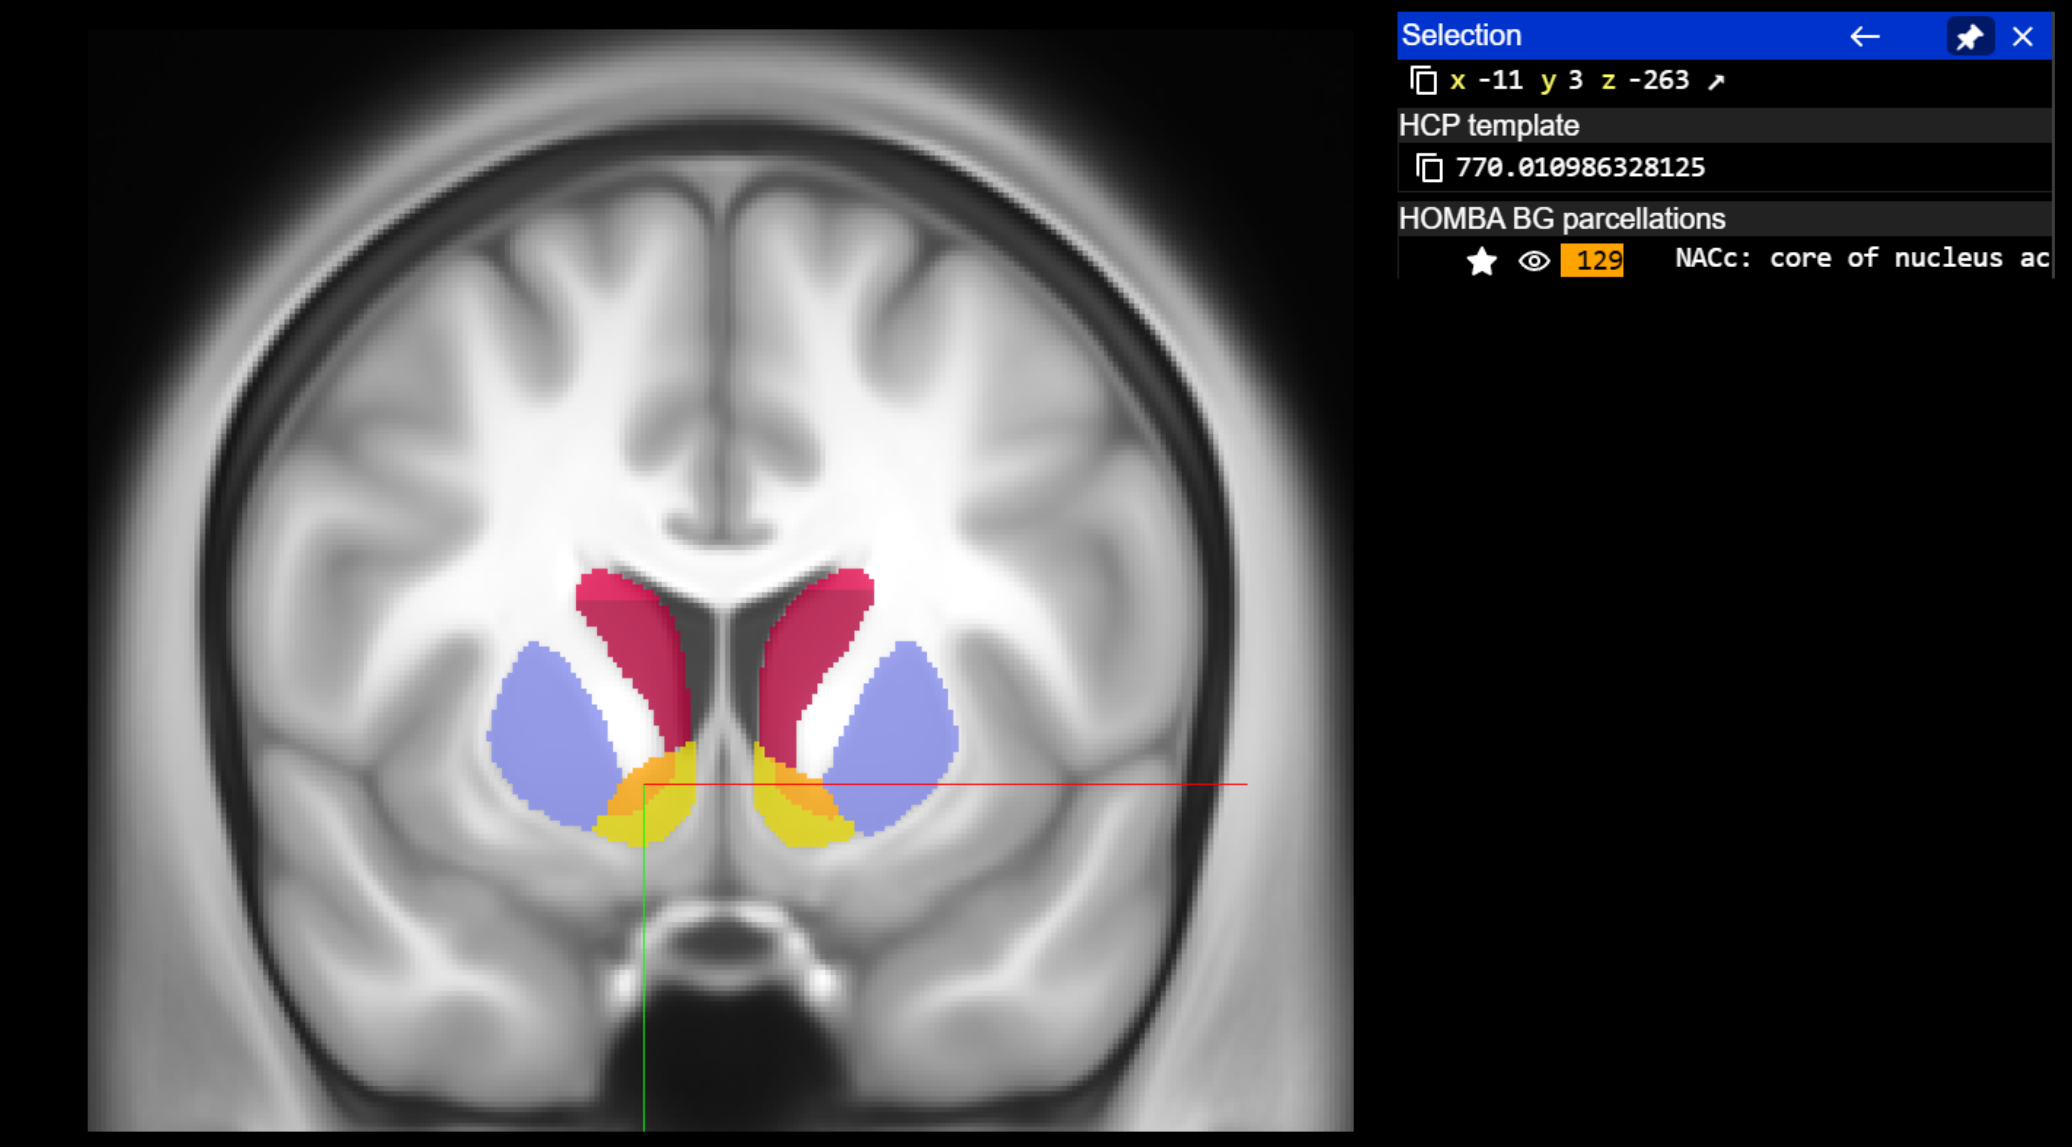

query_coordinate_neuroglancer = [-11, 3, -263]

acronym, name = annotation_image.get_atlas_label(query_coordinate_neuroglancer, physical_coordinate = True, neuroglancer_coordinate=True)

print(f"Coordinate {query_coordinate_neuroglancer} is in {acronym}: {name}")

Coordinate [-11, 3, -263] is in NACc: core of nucleus accumbens